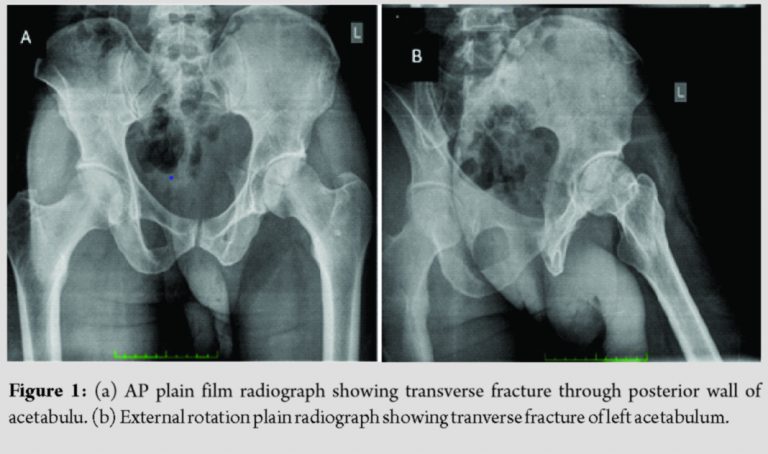

A 51-year-old male amateur endurance runner presented with a 1-day history of sudden onset left hip pain and limp aggravated by weight bearing. The patient was previously well, he had a body mass index (BMI) of 21 and recalls no associated trauma. He also gave no history of any prodromal pain. He described that at the time of injury he had just initiated his training routine with a short sprint when he heard a popping noise localized to the left hip with a subsequent inability to fully weight bear on the left lower limb due to pain. Physical examination revealed normal range of motion at the hip but with pain at the extremes of motion as well as pain on axial compression of the hip. Plain film radiographs revealed nondisplaced transverse fracture of the acetabulum (Fig. 1). T2 weighted magnetic resonance imaging (MRI) demonstrated the same with surrounding bone edema and no evidence of lytic lesions or other pathological processes (Fig. 2). Blood investigations were normal inclusive of calcium, parathrmone and Vitamin D levels. A bone density scan (DEXA) of both hips and lumbar spine was within normal limits. Treatment was initiated with non-weight bearing ambulation for a 6-week period. At the end of the 6-week period, repeat plain film radiographs showed satisfactory healing of the fracture. Gradual weight bearing was permitted. The remainder of his recovery was uneventful.